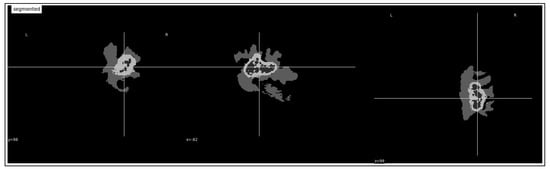

3.3. Tumor Volume Computation

4.3.1. Tumor Identification